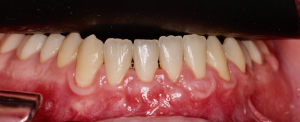

Os enseñamos este nuevo caso el Dr. Arturo Sánchez Colodro en nuestra clínica dental de Jaén, nos muestra un caso donde se puede apreciar con mucha claridad el antes y después de un caso de recesiones inferiores. Este caso ha sido tratado con la última y más avanzada tecnología en digitalización dental.

Exploración intraoral inicial: